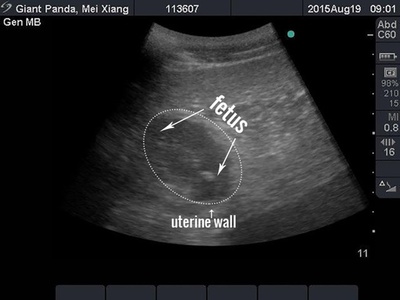

【8月27日 AFP】米首都ワシントン(Washington D.C.)のスミソニアン国立動物園(Smithsonian National Zoo)で26日、前週末に生まれたジャイアントパンダの双子のうち、1匹が死んだ。予想外の双子パンダが生まれた喜びは、わずか4日で悲しみに変わった。

死んだのは母親の「メイシャン(美香、Mei Xiang)」が育児放棄した体の小さい方の赤ちゃん。メイシャンが世話をしている方の赤ちゃんパンダは体重が137.7グラムだが、死んだ方のパンダはその半分の79.8グラムしかなかったという。